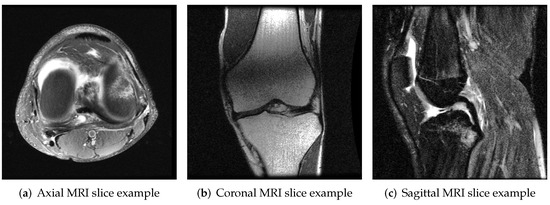

It allows us to take sequences of images called “slices” across three different planes—axial, coronal, and sagittal (presented in Figure 1), building a complete representation of any body part. MRIs provide great insight for expert physicians, including musculoskeletal (MSK) radiologists, who conclude the diagnosis, and choose treatment methods.

Figure 1. Planes of MRI imaging. axial (green), coronal (blue) and sagittal (red).

Figure 2. Input image examples of MRNet. Three images represent (a) axial, (b) coronal and (c) sagittal knee MRI planes.